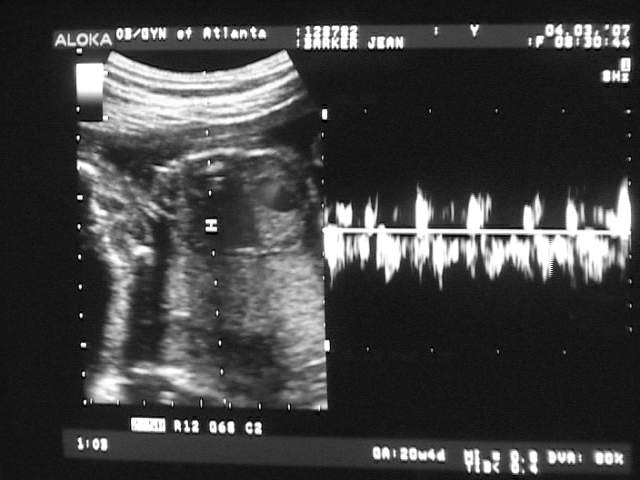

5. It's a Boy!!

• 2009-12-07

• Dave Allen Barker Jr

We got a sonogram today, and we have a boy on the way!

Heartbeat sounds good… [Sonogram]